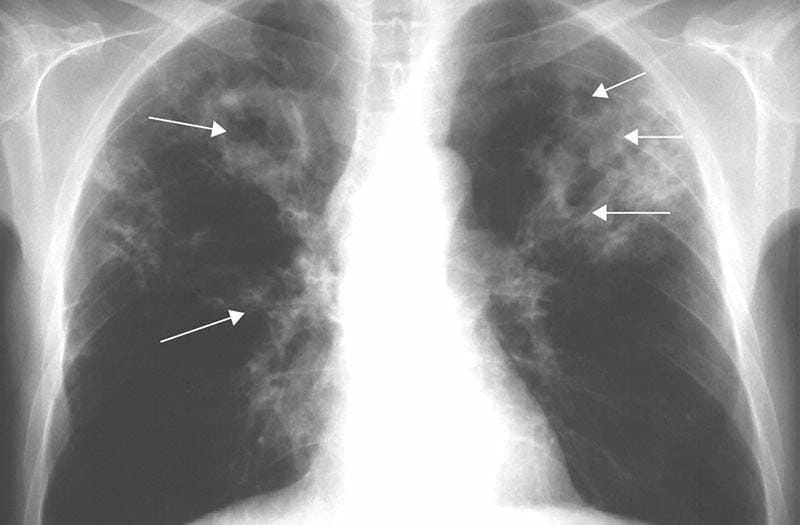

Hình ảnh bệnh lao phổi là tài liệu tham khảo quan trọng giúp người bệnh và bác sĩ dễ dàng nhận biết dấu hiệu bất thường. Việc quan sát hình ảnh X-quang, CT phổi giúp chẩn đoán chính xác mức độ tổn thương và đưa ra phương án điều trị kịp thời.

Bạn sẽ phải rùng mình khi chiêm ngưỡng hình ảnh bệnh lao phổi là như thế nào dưới ống kính y học thực tế. Những bức ảnh chụp X-quang cho thấy phổi bị tổn thương nặng, xuất hiện những đốm trắng mờ như bóng ma ám ảnh. Không chỉ là các tổn thương vật lý, đây còn là những “chứng tích sống” của căn bệnh âm thầm hủy hoại cơ thể qua từng hơi thở. Từ viêm nhẹ đến tổn thương lan rộng, hình ảnh bệnh lao phổi khiến người xem không thể rời mắt vì mức độ nghiêm trọng mà nó thể hiện rõ ràng qua từng chi tiết.

Cảnh báo: tổng hợp ảnh bệnh lao phổi chân thực này không dành cho người yếu tim. Đây là loạt hình ảnh y khoa được các chuyên gia sưu tầm và xác thực, ghi lại quá trình tiến triển của bệnh từ giai đoạn đầu đến giai đoạn nguy kịch. Từng mảng mô phổi bị ăn mòn, xơ hóa, hoại tử được phơi bày rõ nét dưới ánh sáng X-quang lạnh lùng. Những hình ảnh này không chỉ mang tính chất minh họa y học, mà còn là hồi chuông cảnh tỉnh cho bất kỳ ai còn lơ là với căn bệnh nguy hiểm này.